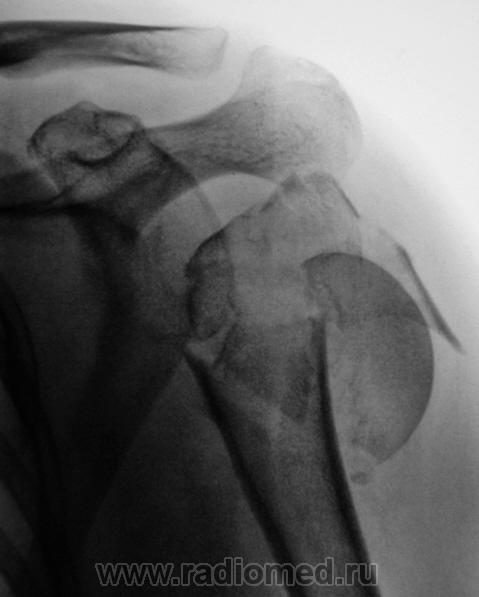

Пациент направлен врачом хирургом поликлиники для рентгенографии плечевого сустава. Травма в день исследования.

перелом головки плечевой кости, со смещением фрагментов кости каудально.